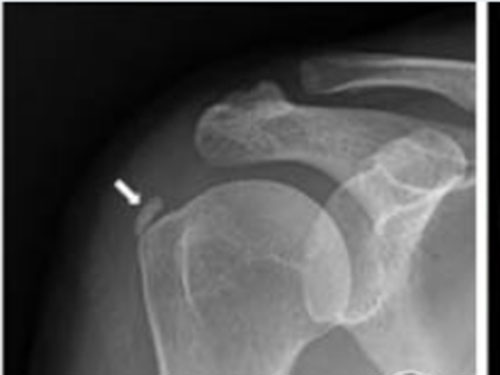

箭头所指为肌腱钙化处

X线片:肩袖组织内高密度影。